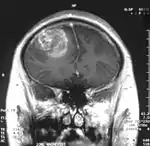

Мультиформна гліобластома (англ. Glioblastoma multiforme, GBM) — найбільш розповсюдженна і найбільш агресивна форма пухлини мозку, яка становить до 52 % первинних пухлин мозку і до 20 % всіх внутрішньочерепних пухлин. Незважаючи на те, що гліобластома є найбільш розповсюдженою первинною пухлиною мозку, на 100 тисяч жителів Європи і Північної Америки реєструється всього 2-3 випадки захворювання[3]. Термін «гліобластома» передбачає два варіанти цієї хвороби: гігантоклітинна гліобластома і гліосаркома.